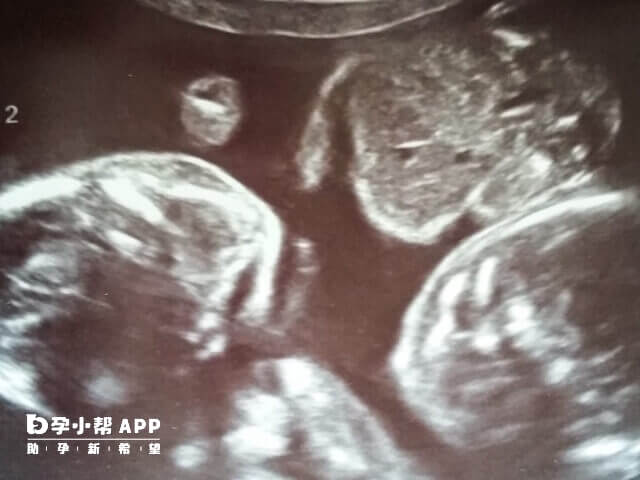

5、如果是需要龙凤胎的宝妈就需要移植一个男性胚胎和一个女性胚胎,如果是双胞胎的话就需要移植两个男性胚胎;